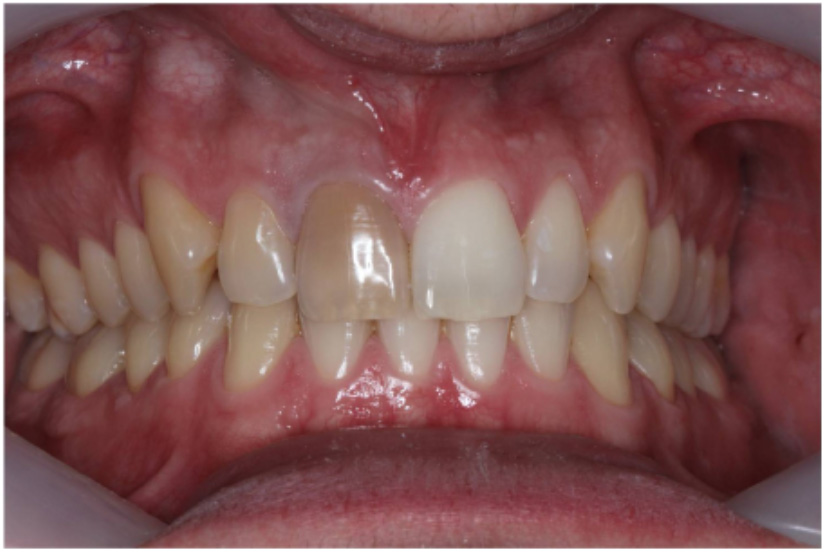

Preoperative assessment (Figure 6)

- Clinical assessment

- The tooth should be asymptomatic prior to considering bleaching

- Radiographic assessment

- The tooth should have a good quality root canal filling with no evidence of periapical pathology. If there are any problems then root canal retreatment is required (even if the patient is asymptomatic)

- Clinical photographs

- Clinical records to show the initial shade. Including a shade tab can be helpful.